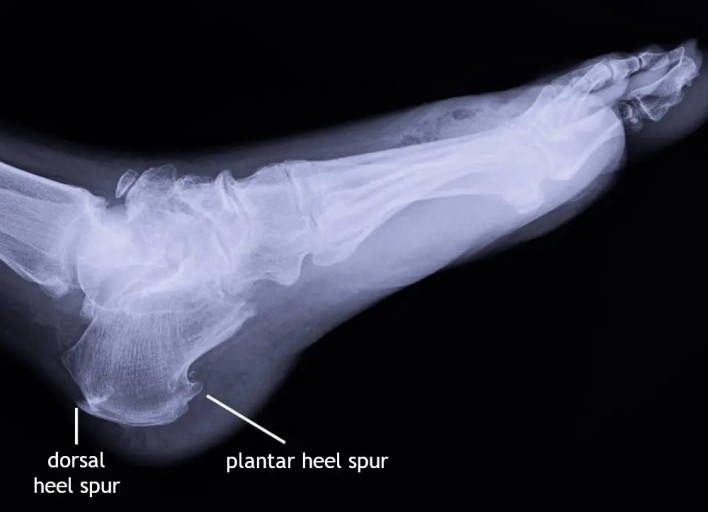

초기에는 밤에만 불편함을 느끼다가 점점 지속 시간도 늘어납니다.3. 족저근막염

발바닥 통증의 대표 질환으로,

발뒤꿈치에서 발바닥 전체로 이어지는 근막에 염증이 생기며

걷거나 서 있을 때 발바닥이 뜨겁고 찌릿한 통증을 유발합니다.

특히 아침에 첫 발을 디딜 때 더 아픈 경우가 많아요.